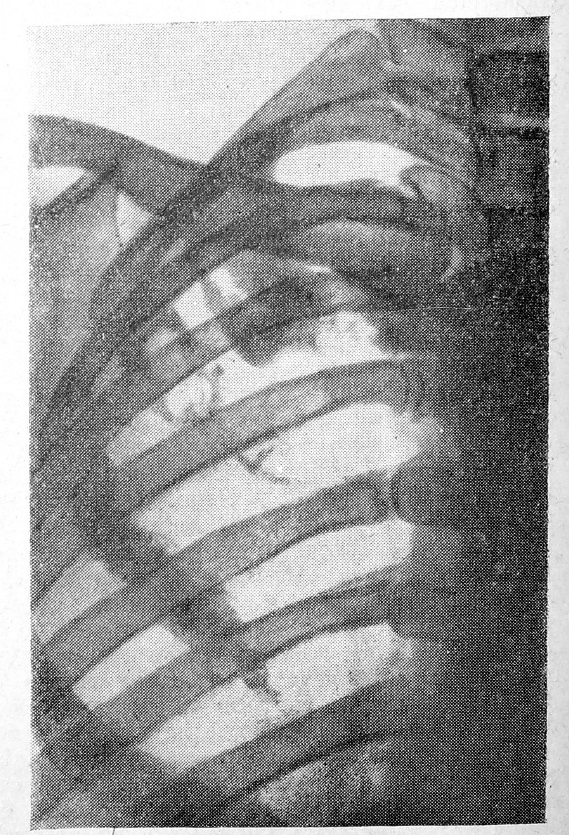

Рис. 2. после лечения

На контрольных рентгенограммах вскоре после лучевой терапии, несмотря на удовлетворительный клинический результат, перемен в большинстве случаев не отмечалось. При рентгенологическом контроле через 5—6 месяцев, чаще через 8 месяцев, наблюдалось отложение солей кальция — развитие реактивного »остеосклероза в месте поражения (рис. 1, 2). По нашим данным, наиболее отчетливое склерозирование пораженной кости происходило после облучения плоских костей (ребра, грудины, лопатки).